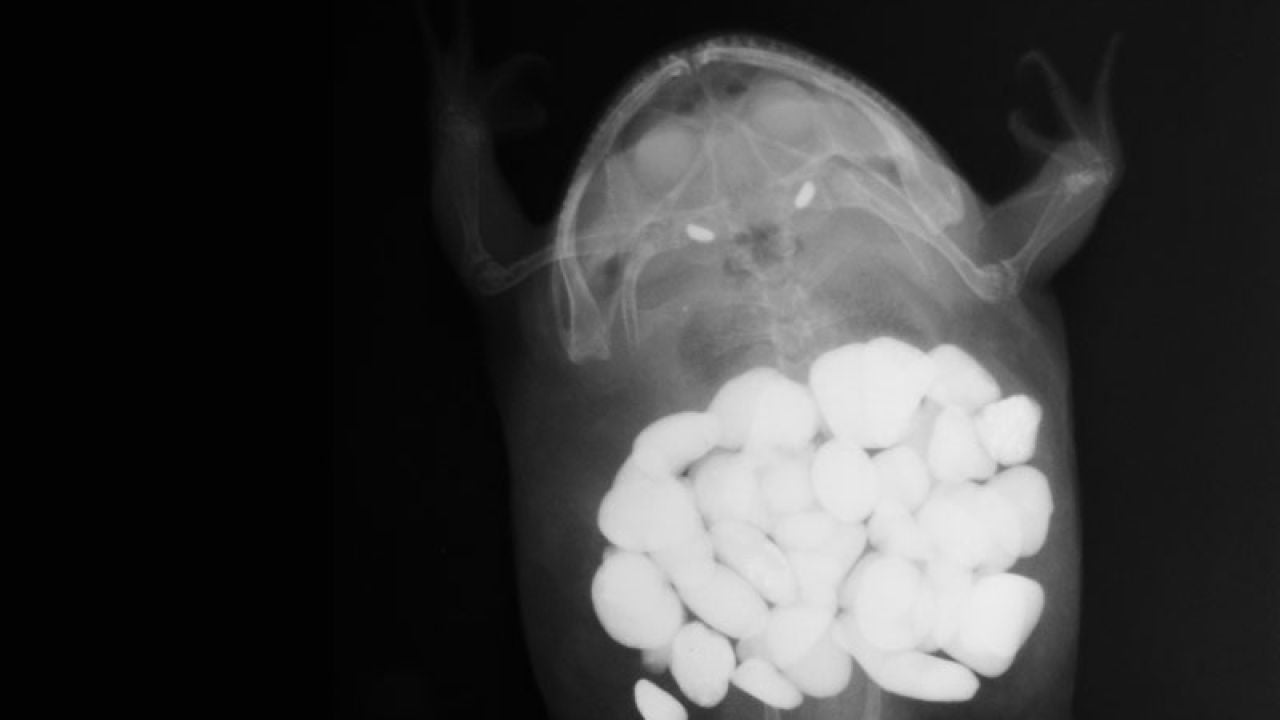

El estómago de una rana con unas 30 piedras de decoración | veterinarypracticenews.com Esta radiografía muestra 43 calcetines estómago de un Gran Danés | veterinarypracticenews.com Una navaja en un perro labrador | veterinarypracticenews.com Un extraterrestre de juguete en el cuerpo de un gato | veterinarypracticenews.com Una bombilla encontrada en un perro golden retriever | veterinarypracticenews.com El cuerpo de una rana con un plátano de juguete en su interior | veterinarypracticenews.com Un brocheta de cocina en el cuerpo de un perro | veterinarypracticenews.com Más sobre este tema: perros gatos